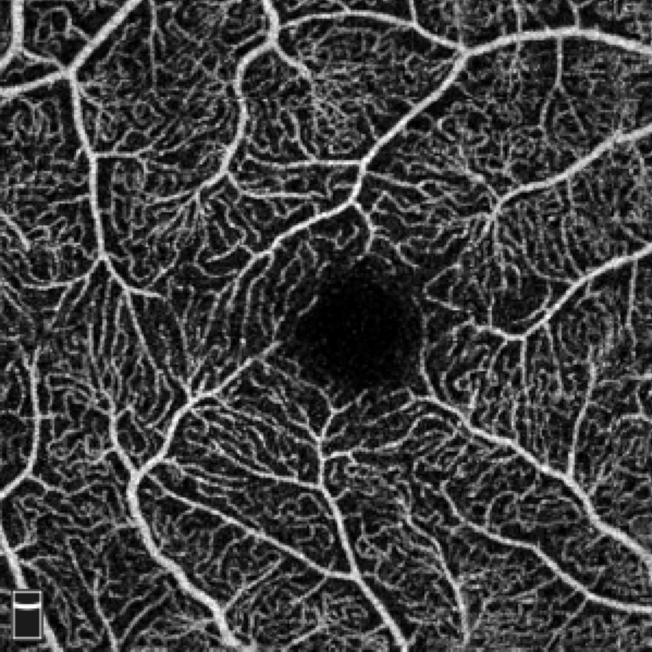

Instead of solely analyzing the signs and magnitudes of the Hessian eigenvalues as in the traditional Frangi filter, we propose to leverage the eigenvectors along with custom-designed magnitudes to create our tensor field as shown in Fig. 3(Left). The core idea of Frangi filter is to enhance the tubular structure by matching the vessel diameter with the distance between the two zero crossings in the second order derivative of Gaussian ( ). However, the solution is not guaranteed to land in range , especially for small vessels. Consequently, we observe that the inaccurate estimation of results in a blurring effect at the vessel boundary, which is problematic for segmentation. As an example in Fig. 3(Left), the direction of at aligns with that at , even though is inside the vessel while is in the background but close to the boundary. This makes it difficult for the vector orientations alone to differentiate points inside and outside the vessel. To tackle this, we introduce the idea of a bipolar tensor by assigning a large magnitude to the orthogonal eigenvector to points in the background, as shown in the blue dashed ellipse. Specifically, we define the magnitudes and associated with the eigenvectors and as:

| (3) |

where is the probability that the intensity of a random pixel in the image is greater than . This is equivalent to normalizing the histogram by the factor and computing the cumulative distribution function at . This term thus provides a normalized brightness function in the range . The exponential term represents how vessel-like the voxel is by using a normalized eigenvalue, and is in the range as well. is a constant that controls the sensitivity, which is empirically set to . With the custom magnitudes and , the two poles can better differentiate vessels from the background. Fig. 3(Right) is an example of BTF on an OCTA image. In practice, we stack the two vectors as the input to the structural encoding network, i.e., .